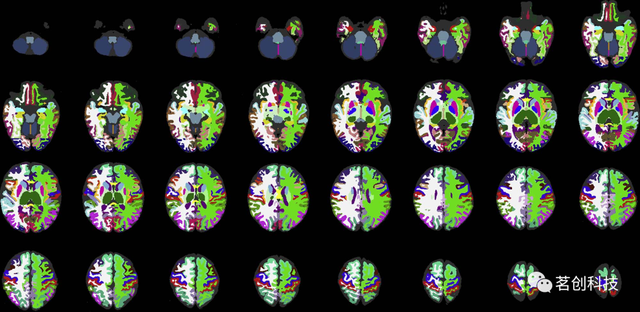

JHU-neonate-SS图谱

该图谱来自一个典型发育的足月婴儿,在出生后两天进行扫描。大小和形状与人口平均的JHU新生儿线性模板相匹配。该图谱由共同配准的T1、T2加权和DTI组成,其分割图包括130个解剖标签,包括54个皮层区域、56个白质结构、14个深部灰质结构和6个脑干结构覆盖整个大脑。手工绘制的分区图遵循成人JHU-MNI分区图,这使得成人和新生儿大脑之间的结构比较成为可能。其优点是多模态性能和当前婴儿大脑分割图中最精细的粒度。还提供了组平均T1和T2加权和DTI模板(JHU-neonate-linear和JHU-neonate-nonlinear)。

基于标签的脑ROI模板(ALBERT)

这是一组不同年龄的婴儿大脑图谱,其中包括来自20名足月和早产儿在矫正胎龄后第36-45周扫描的T1和T2加权图像,以及由50个手动划分的结构组成的分割图。

爱丁堡新生儿图谱(ENA33)

这是一组共同配准的T1和T2加权图像、DTI和33名正常发育的足月新生儿的分割图,这些新生儿在37-41周进行扫描。分割图由107个解剖区域组成,这些区域来自成人脑图谱(SRI24/TZO);

https://www.nitrc.org/projects/sri24。这在当前的婴儿大脑多图谱存储库中具有最精的细粒度。

M-CRIB图谱

这是一组来自10名健康足月新生儿的T2加权图像,并附有复证Desikan-Killiany成人皮层图谱的分割图,该图谱将大脑分割成100个区域,分割是手动完成的。而且还提供了组平均T2加权结构模板。

MRICloud 新生儿多图谱库

这是一组由7名健康足月新生儿的T1加权图像组成,并附有复证MRICloud成人图谱库的分割图,该库将整个头部分割成30个区域,分割是手动进行的。全脑覆盖允许对颅腔内容积进行量化,这是其他婴儿图谱集无法提供的。